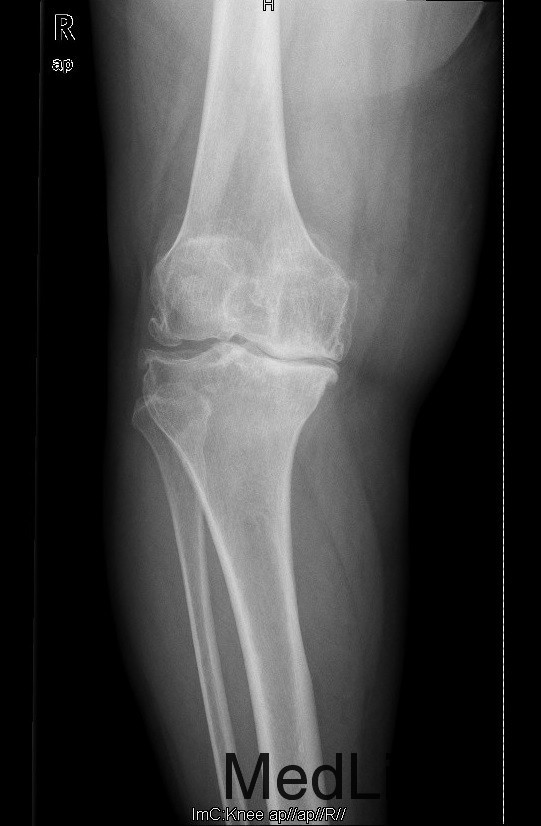

查体:步态跛行,双膝屈曲畸形,左膝外翻、右膝内翻畸形,双膝内外侧关节间隙及髌股关节间隙压痛明显,右侧重,右膝内翻:5°,右膝屈70°,伸-10°;左膝:屈曲:100°,伸:-5°,外翻:20°,双膝主被动屈伸活动时疼痛,双膝髌下摩擦音(+)。 辅助检查:右膝关节间隙狭窄,软骨下骨硬化,髌股关节间隙消失,左膝关节间隙狭窄,软骨下骨硬化,髌股关节间隙狭窄,双膝髌骨、股骨、胫骨周围大量骨赘形成,关节腔内均可见游离体。

诊断:1.双膝重度骨关节炎继发右膝屈曲内翻畸形,左膝屈曲外翻畸形(Krackow Ⅰ型)2.高血压病(3级 极高危) 治疗:积极行术前准备,待血压等稳定后于全麻下行右侧全膝关节置换术,术后常规治疗,并鼓励其锻炼。